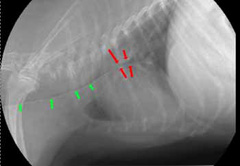

Коллапс трахеи форум

Коллапс трахеи форум 116 фотографий